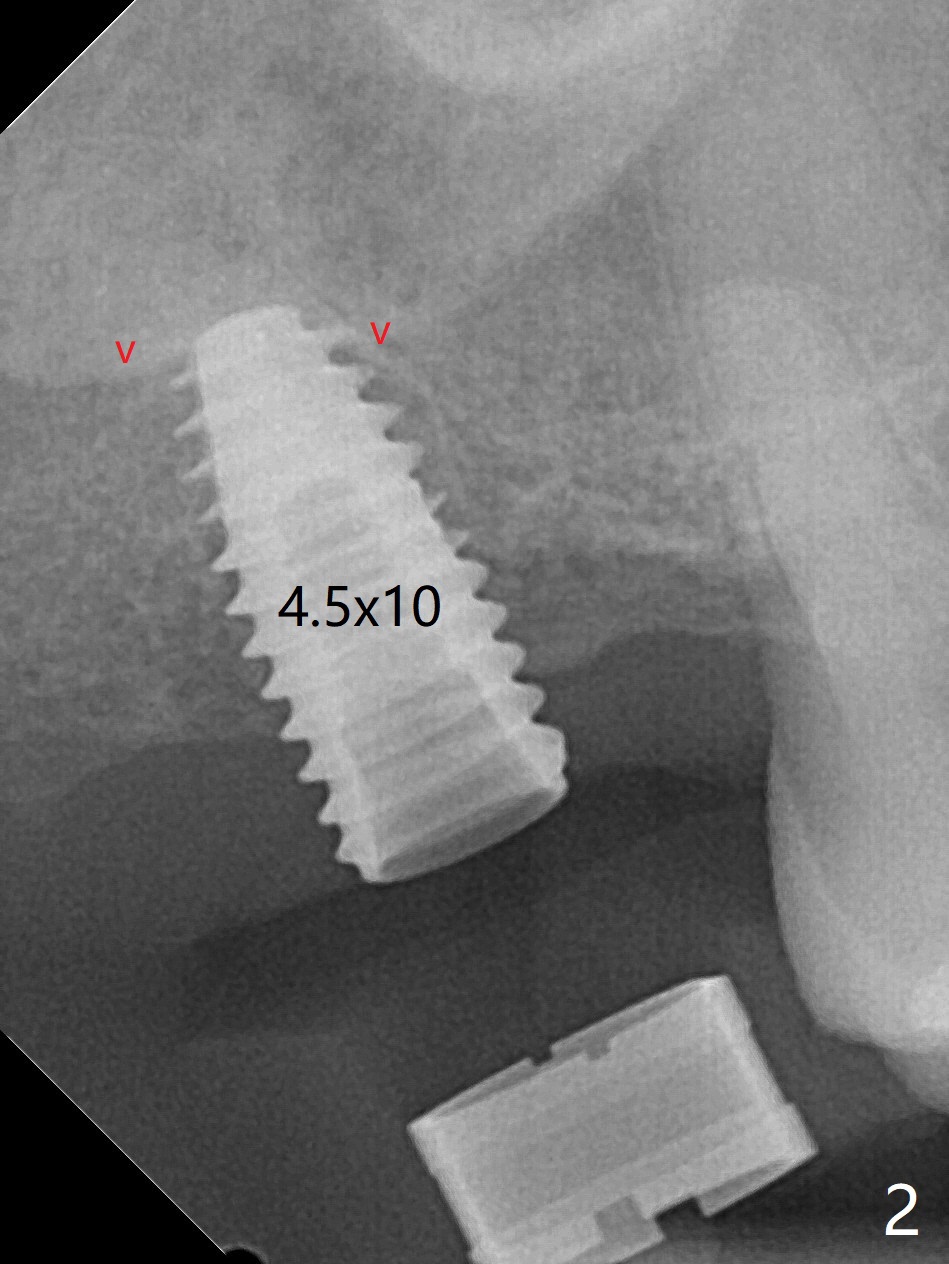

尽管事先准备15号刀片,看到完整2号牙牙槽嵴就舍不得切开。放置以前导板(用于即种),用软组织环形刀做个记号,接着用活检环形刀切取钻洞表面软组织,保存于PRF液体中。术前CT显示3号牙上方粘液囊肿(图一:*),而2号牙上方窦膜薄,总之两者都不好惹(容易感染,窦膜破),提升需要特别小心。完成初步钻洞后,使用17-19毫米长的DIO圆钻,放置粘性骨粉,使用4.5x10毫米报废植体进行提升(到第一横线),结果窦底没有穿(图二:红箭头)。接着使用尖头钻头从原来2.2x5.3毫米一直到3.5x10毫米,几乎每使用一个钻头后都检查窦底完整性,再放置骨粉,使用4.0x10毫米植体提升(到第二横线),好像穿过窦底(图三)。再加骨粉,使用4.5x10毫米植体扭力底,最后放置PRF膜,很难塞入上颌窦,结果只能从钻洞上端近中很小裂口塞入,植入5x8.5毫米正式植体(图四),上颌窦里骨粉呈蘑菇状(*)。临床检查腭侧(P)植体牙槽嵴下,其余骨壁难于判断。而咬翼片却显示植体颊侧(B),腭侧均在牙槽嵴下(图五)。为了减少术后骨质吸收,放置愈合螺帽后(图六:S),植体表面添加骨粉(*),最终把保存的软组织放回原位(二期手术:减少上颌窦与口腔交通,感染),牙周胶水粘固(图七)。术后没有鼻出血。